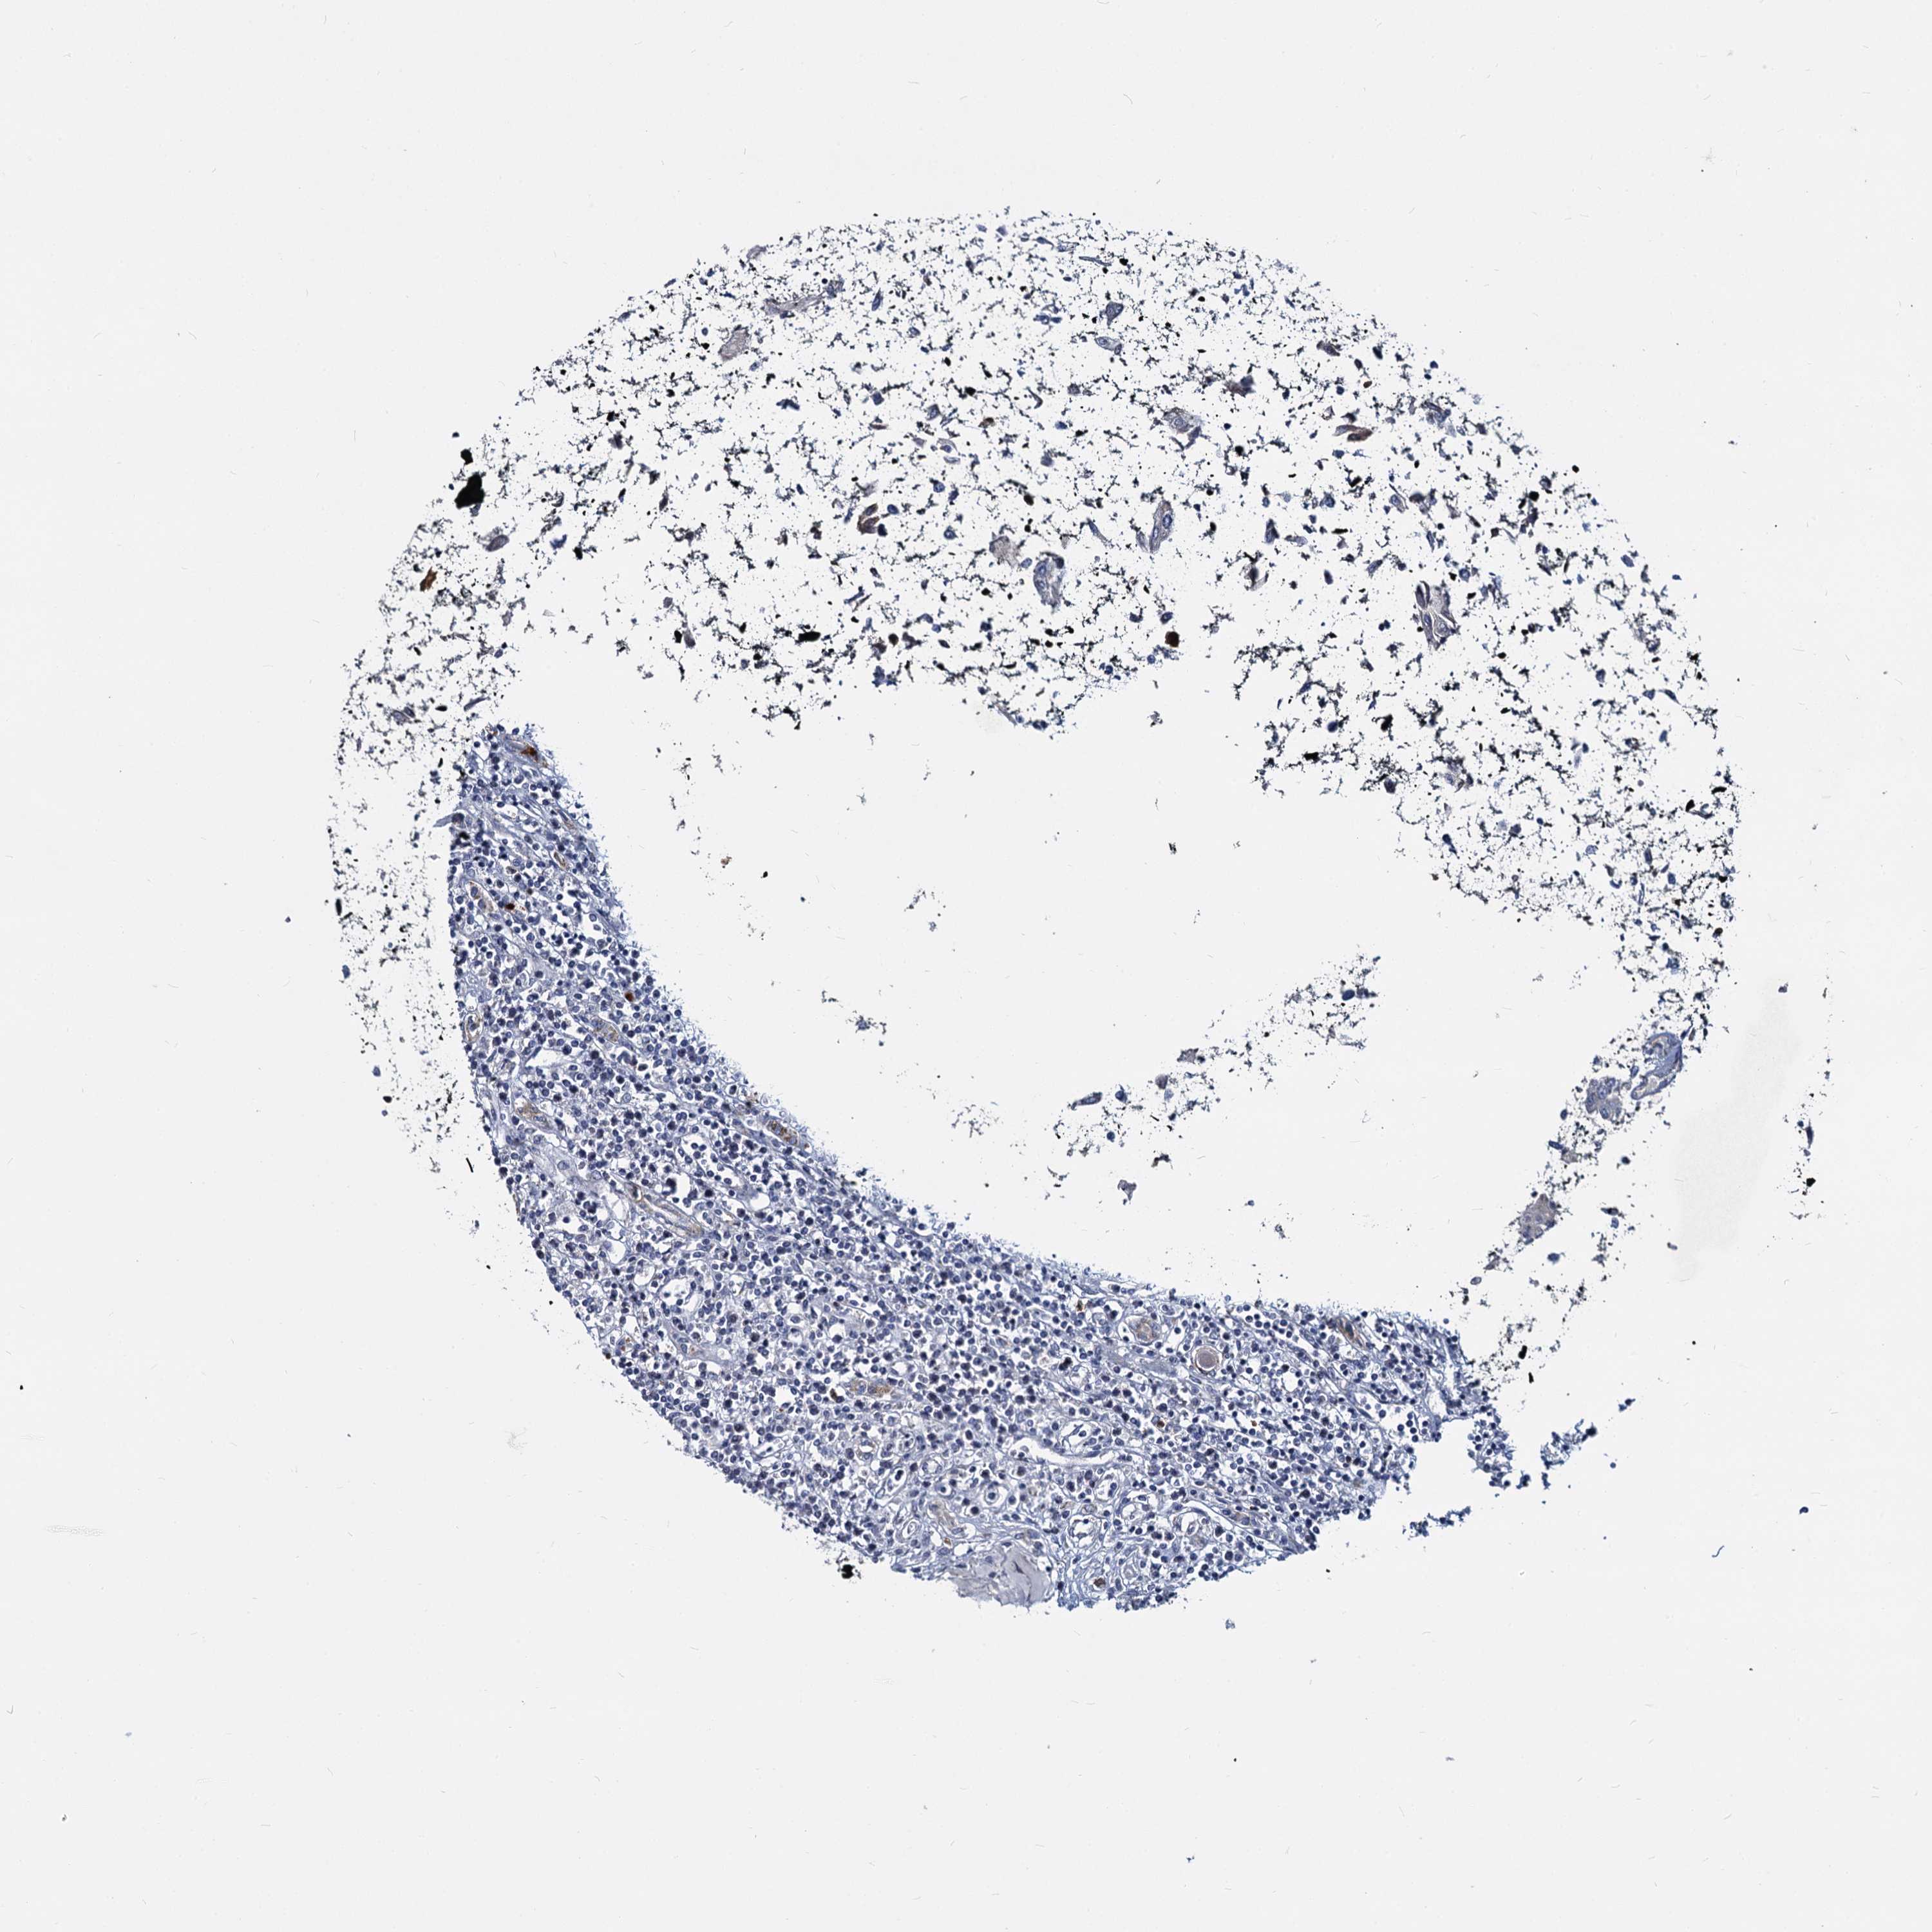

CANCER RENAL CANCER Show tissue menu

KICH TCGA KIRC TCGA KIRC VALIDATION KIRP TCGA PROTEIN RCC CPTAC PROTEIN EXPRESSION